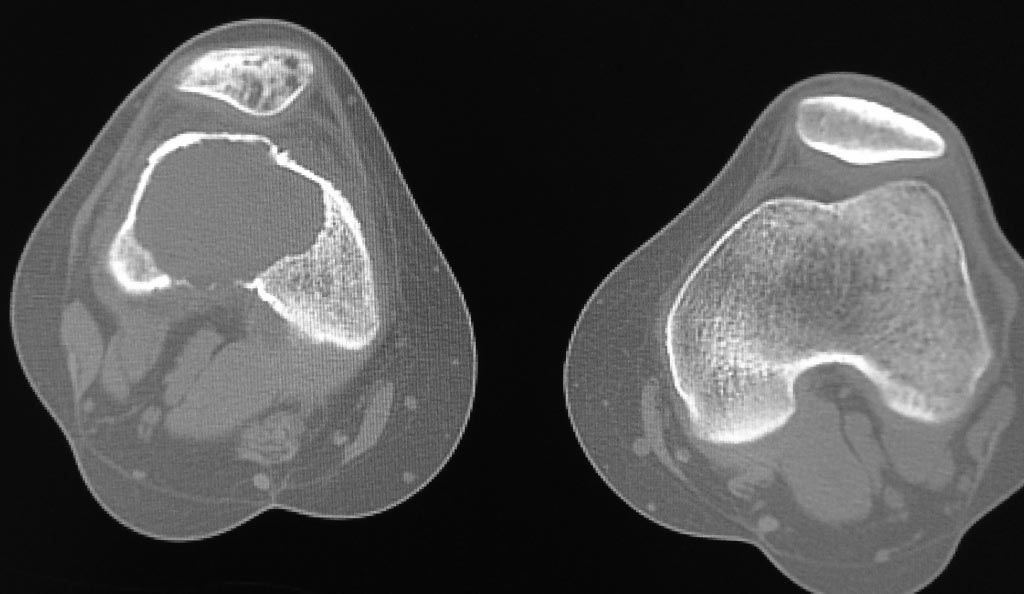

прилагаю МРТ и КТ. Образование накапливает радифармпрепарат :(

Снимки

Некоторые считают, что диагноз ОБК - рентгенологический. Гистологию можно и не получить, мы как-то удаляли, отправляли с фрагментами костной ткани интраоперационно - результат 0. Зато я видел 2-х пациентов с гнойными осложнениями после биопсии (кровь течет, рана не может закрыться) от которых отказывались и ортопеды (гной мы не лечим) и онкологи (в такой ситуации можем отпилить ногу/руку). Оперировал похожий случай 1 раз, вынужденно - с квотами были проблемы, пациентка была у же во всех лечебницах города - везде пнули. Только был проксимальный метафиз б/б кости, но почти полностью. Зашли через окно снаружи, максимально радикально острыми ложками, иногда долотом обработал края раны, промыл йодом, обработал азотом (криодеструкция - опционно, у нас такая возможность была и нам это показалось полезным), полость заместил костным цементом. пока результат 4 года, рецидива нет. даже заднемедиальный участок до которого я не добрался - склерозировался. В вашем случае меня больше смущает надколенник, возможно подскажут более опытные коллеги.

Внешне похоже на ОБК. Другой вариант - аневризмальная киста, но вряд ли (на МРТ обычно видны множественные уровни жидкости).